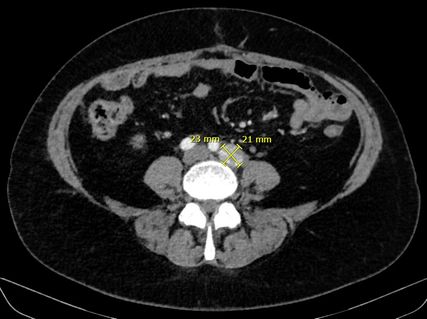

Abb. 2:„Stable disease“ der parailiakalen Lymphknotenmetastase nach sieben Zyklen Immuntherapie

Basierend auf den Ergebnissen der Phase-III-Studie DUO-E wurde eine Erweiterung der systemischen Therapie empfohlen. In DUO-E hatte die Zugabe des PARP-Inhibitors Olaparib zu dem PD-L1-Inhibitor Durvalumab im Sinn einer onkologischen Vierfachtherapie bei non-dMMR-Karzinomen zu einer signifikanten Verlängerung des progressionsfreien Überlebens geführt.1 Die Kombinationstherapie wurde von der Patientin ohne Hinweis auf „immune-related adverse events“ (irAEs) gut vertragen. Serologisch zeigte sich eine Remission mit normwertigen Tumormarkern und radiologisch eine stabile Erkrankung mit größenkonstanten Lymphknotenmetastasen. Die Abbildungen zeigen den Zustand nach sechs Zyklen Chemo- und zwei Zyklen Immuntherapie (Abb.1) sowie nach sieben Zyklen Immuntherapie (Abb.2). Die Patientin befindet sich aktuell weiterhin unter laufender dualer Erhaltungstherapie mit Durvalumab – zuletzt Zyklus 10 – und Olaparib.